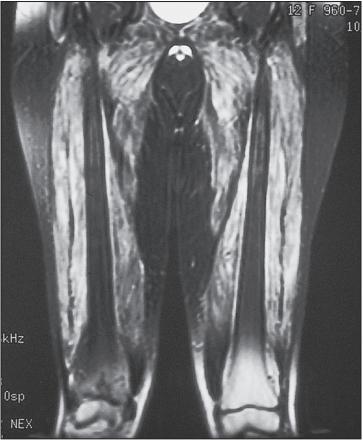

肌肉活检的光镜检查

但是如何做肌肉活检?仅仅根据症状就行肌肉活检是不妥的。尤其采用医生体检按压肌肉寻找肌肉活检部位。这是因为临床按压本身可能误导肌肉活检结果。为此,予以磁共振(MRI)检查肌肉是必要的。因为MRI对早期肌组织病变和钙质沉着敏感。采用T2加权和压脂序列可以清楚显示病变范围,提高肌电图及肌活检的阳性率。虽然「皮肌炎和多发性肌炎」临床表现为对称性近端肌肉受累,但MRI可以呈现不均匀和不对称性。MRI阳性改变在一些血清肌酶正常的「皮肌炎和多发性肌炎」中亦不少见。因此, 可用于评估疾病活动性、 累及损害和对治疗的反应。

一儿童皮肌炎的MRI压脂图像显示,关注白色提示肌肉炎症